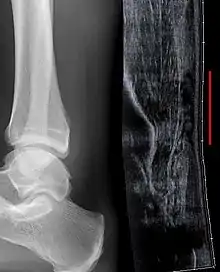

Although a tear may be diagnosed by history and physical exam alone, an ultrasound scan is sometimes required to clarify or confirm the diagnosis. Once diagnosis is made, ultrasound imaging is an effective way to monitor the healing progress of the tendon over time. An ultrasound is recommended over MRI and MRI is generally not needed.[11][14] Both MRI and ultrasound are effective tools and have their strengths and limitations. However, when it comes to an Achilles tendon tear, an ultrasound is usually recommended first because of convenience, quick availability, and cost.[15]

Imaging

Ultrasonography can be used to determine the tendon thickness, character, and presence of a tear. It works by sending harmless high frequencies of sound waves through the body. Some of these sound waves reflect back off the spaces between fluid and soft tissue or bone. These reflected images are analyzed and created into an image. These images capture in real time and are helpful in detecting movement of the tendon and visualizing injuries or tears. This device makes it possible to identify injuries and observe healing over time. Ultrasound is inexpensive and involves no harmful radiation. It is operator-dependent and so requires a level of skill and practice for it to be used effectively.[15]

MRI can be used to distinguish incomplete ruptures from degeneration of the Achilles tendon. MRI can also distinguish between paratenonitis, tendinosis, and bursitis. This technique uses a strong uniform magnetic field to align millions of protons running through the body. These protons are then bombarded with radio waves that knock some of them out of alignment. When these protons return they emit their own unique radio waves that is analyzed by a computer in 3D to create a sharp cross sectional image of the area. MRI provides excellent soft tissue imaging making it easier for technicians to spot tears or other injuries.[16]

Radiography can also be used to indirectly identify Achilles tendon tears. Radiography uses X-rays to analyze the point of injury. This is not very effective at identifying soft tissue injuries. X-rays are created when high energy electrons hit a metal source. X-ray images are acquired by utilizing the different densities of the bone or tissue. When these rays pass through tissue they are captured on film. X-rays are generally best for dense objects such as bone while soft tissue is shown poorly. Radiography is not the best for assessing an Achilles tendon injury. It is more useful for ruling out other injuries such as heal bone fractures.[14]